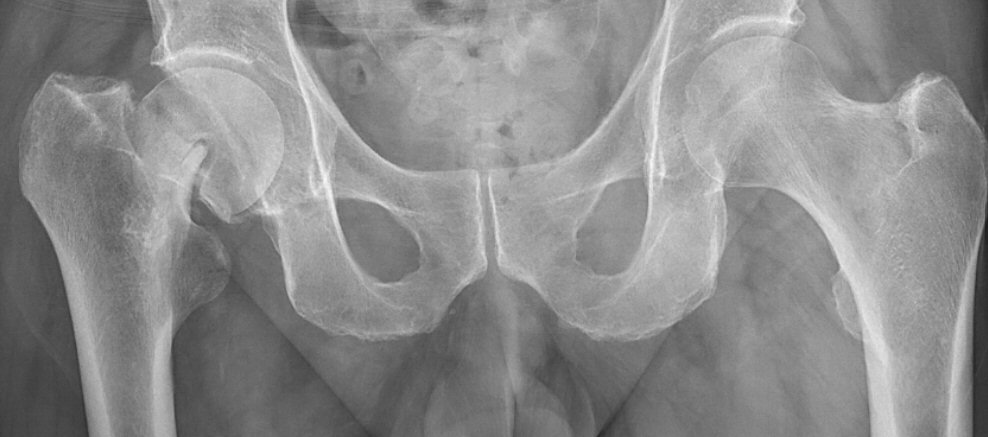

- Värdera om benet är rätt (ska vara 15° inåt) och sidlikt roterade. Trokanter minor bör vara symmetriska på vänster och höger sida. Vid fraktur så brukar det frakturerade benet vara utåtroterat.

- Värdera om röntgenbilden är tagen rakt framifrån. I så fall bör coccyx och symfysen ligga över varandra och foramina obturatoria bör vara symmetriska.

Första bilden är nästan rak frontal med överlappande coccyx och symfys samt symmetriska foramina obturatoria. Andra bilden är inte rak.